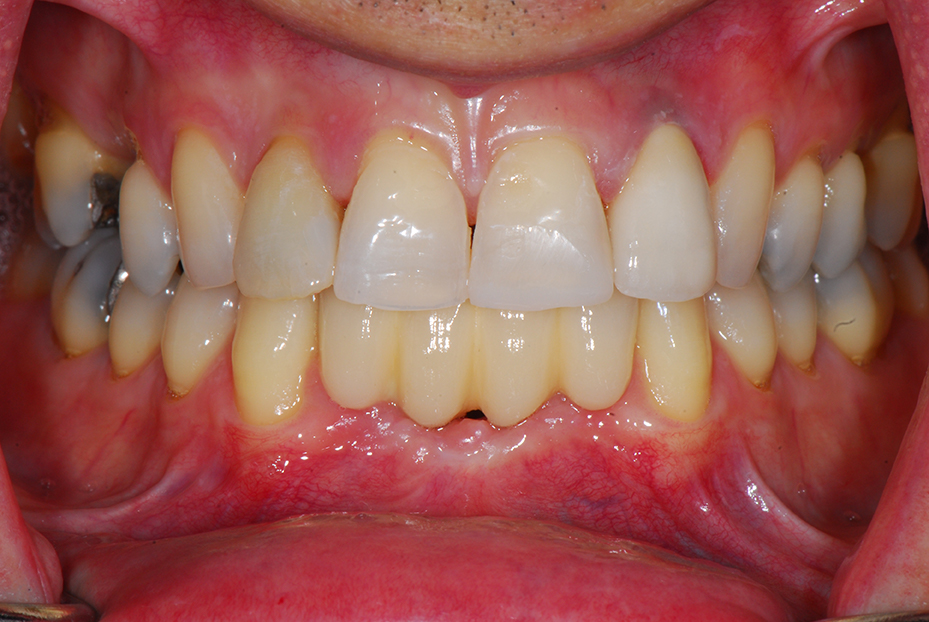

Replacement of all four failing lower front teeth with an implant bridge, some whitening, composite bondings and one new crown on an upper lateral incisor